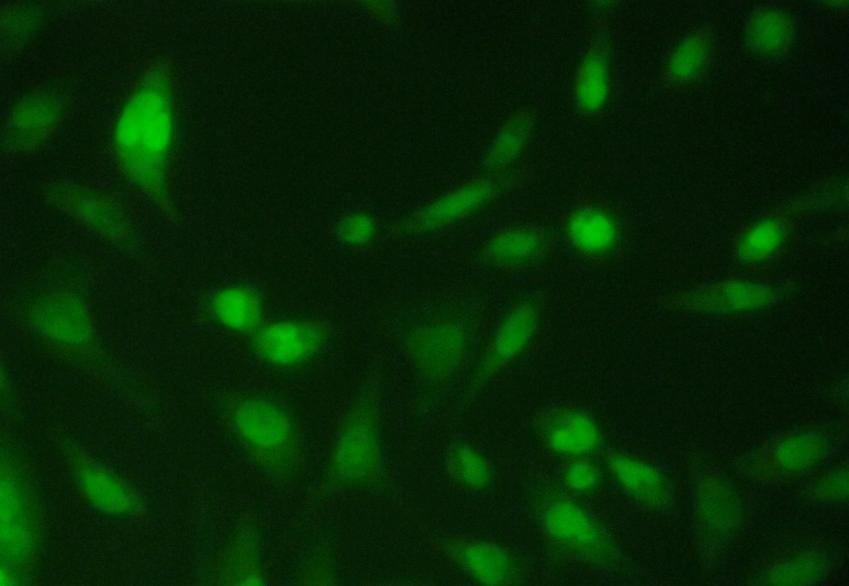

To better understand morphological change of Hep 3B cells after silver nanoparticles treatment, the cells were observed under acridine orange/ethidium bromide (AO/EB) double staining after treatment at different time points of silver nanoparticles. The figure shows. that the Silver Nanoparticles induced apoptosis after 24 and 48 hours incubation. Cells stained green represent viable cells (Figure 4a), whereas bright greenish yellow staining represented early apoptotic cells, and reddish or orange staining represents late apoptotic cells. As shown in (Figure 4b) Hep 3B cells after 24 hours treatment showed slight changes in cellular morphology, including chromatin condensation and fragmented nuclei. On the other hand, (Figure 4c) show higher number cells with increased chromatin condensation with increased fragmented nuclei thus it represents increase in the number of apoptotic cells after 48 hours of treatment.

Fig. 4b: 24 hrs after treatment of Hep 3B cell line with IC50 concentration

Fig. 4c: 48 hrs after treatment of Hep 3B cell line with IC50 concentration

Therefore, using the AO/EB staining procedure, the morphological features of a Hep 3Bcell line in apoptosis were time dependent, i. e., a stronger apoptosis signal was induced with increase in the time. The cytotoxic effects of SNPs, probably due to the fact that SNPs may interfere with the proper functioning of cellular proteins and induce subsequent changes in cellular chemistry [17.18] reported a significant cytotoxicity of AgNPs in BRL 3A rat liver cells.